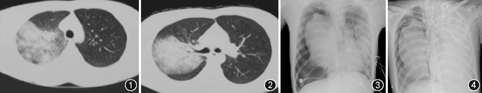

患者男,31岁,因"发热、咳嗽、胸痛3 d,呼吸困难6 h"于2018年5月12日入住中日友好医院。患者2018年5月9日出现发热,体温最高达39.5 ℃,无畏寒、寒战,伴咳嗽,咳黄白色黏痰,痰中偶有带血,感右侧胸背部疼痛明显,就诊于当地诊所,服用"罗红霉素"效果不佳。入院前除就诊1次外,均在家中休息,无其他辅助检查结果。入院当天因胸背部疼痛加重,在当地医院查血常规:白细胞计数为12.2×109/L,中性粒细胞占0. 94;胸部CT示右肺上叶大片实变影伴空洞形成(图1,图2)。入院前6 h患者出现呼吸困难并进行性加重,转至中日友好医院急诊。查血常规示:白细胞计数为4.03×109/L,中性粒细胞占0.92,血红蛋白为150 g/L,血小板计数为107×109/L;降钙素原为16.2 μg/L;丙氨酸氨基转移酶为45 IU/L,总胆红素为14.7 μmol/L,直接胆红素为11 μmol/L,总蛋白为58 g/L,白蛋白为37 g/L,乳酸脱氢酶为696 IU/L,肌酸激酶同工酶为45 IU/L,尿素为21.2 mmol/L,肌酐为351.6 μmol/L,电解质正常;肌钙蛋白T为0.73 μg/L,N端脑钠肽前体为25.3 μg/L;动脉血气分析(FiO21.0):pH值为7.10,氧分压为57 mmHg(1 mmHg=0.133 kPa),二氧化碳分压为57 mmHg,碳酸氢根为17.7 mmol/L,剩余碱为-12.4 mmol/L,乳酸为5.7 mmol/L。给予无创呼吸机辅助通气,1 h后复查动脉血气示酸中毒及氧合水平无改善,且出现嗜睡状态。随后收入呼吸与危重症医学科监护病房。

入院查体:体温36.2 ℃,脉率154次/min,呼吸37次/min,血压84/50 mmHg,嗜睡状态,四肢冰凉,口唇发绀,右肺呼吸音低,双肺散在湿性啰音,心律齐,各瓣膜区未闻及杂音。动脉血气分析(FiO21.0):pH值为7.06,氧分压为60.8 mmHg,二氧化碳分压为72.4 mmHg,碳酸氢根为16.4 mmol/L,乳酸为5.8 mmol/L;血常规:白细胞计数为1.09×109/L,中性粒细胞计数为0.5×109/L,血红蛋白为158 g/L,血小板计数为93×109/L;肝功能大致正常,尿素为23 mmol/L,肌酐为410 μmol/L;降钙素原为23.3 μg/L;肌钙蛋白T为1.0 μg/L,N端脑钠肽前体>35 000 μg/L;活化部分凝血活酶时间为52.5 s,D-二聚体为2.78 mg/L。床旁X线胸片可见右侧气胸,肺叶压缩约50%,右肺均匀致密影,左肺团片致密影(图3)。

2018年5月14日气管镜检查见气管黏膜轻度充血水肿,隆突锐利,双肺各叶段黏膜充血水肿较明显,可见中等量黄褐色稀薄分泌物(图4)。BALF培养结果为铜绿假单胞菌,药敏试验结果见表1。同时,患者右侧胸腔闭式引流液为黄色浑浊液体,经反复送检,培养结果与BALF相同。其他细菌、病毒、真菌、结核等检查均阴性。在明确病原学后,抗菌药物调整为亚胺培南/西司他丁+万古霉素。